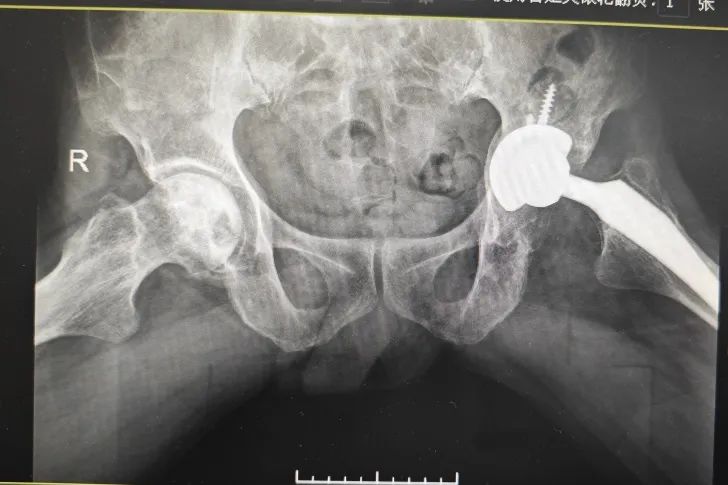

我院關(guān)節(jié)外科團(tuán)隊(duì)完成首例復(fù)雜全髖關(guān)節(jié)翻修重建手術(shù)

近日,我院關(guān)節(jié)外科團(tuán)隊(duì)完成了一例復(fù)雜全髖關(guān)節(jié)翻修重建手術(shù)治療,這也是我院建院以來(lái)首例全髖關(guān)節(jié)翻修重建手術(shù)。該例手術(shù)的圓滿成功,不僅是我院骨科關(guān)節(jié)外科發(fā)展邁入新階...